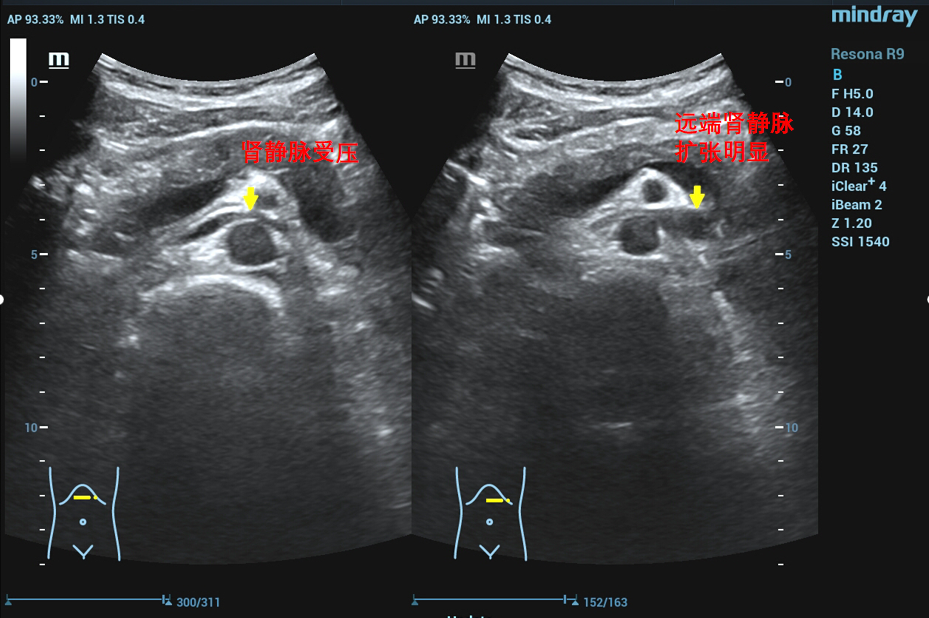

在泌尿外科三病区柯昌兴主任、杨博伟副主任医师、李宇航博士团队的精心准备和密切配合下,顺利为患者完成“腹腔镜(3D)下左肾静脉外支架置入术”。术中,见左肾有3根动脉,其中一根动脉绕行并压迫左肾静脉(术前阅片已确认),左肾静脉入肠系膜上动脉与腹主动脉夹角处,其周围纤维条索较多,此处左肾静脉明显变窄,离断纤维条索后此处左肾静脉明显增宽,充分游离左肾静脉近端至下腔静脉,远端至“其中一根动脉绕行并压迫左肾静脉”处,离断左性腺静脉和肾上腺中央静脉。柯昌兴主任团队成功放置一根6cm长带外支撑环的人工血管固定在患者左肾静脉外面,为受压的左肾静脉支撑起一条“生命通道”,提供持久的支撑力对抗肠系膜上动脉和腹主动脉的压迫。整个手术非常顺利,耗时约3小时,出血约10毫升。术后3天,患者康复出院,且腰痛、血尿等术前临床症状明显缓解,手术效果非常显著。

胡桃夹综合征,也称胡桃夹现象。是指左肾静脉回注下腔静脉过程中,需穿经由腹主动脉和肠系膜上动脉形成的夹角内受到挤压而引起的血尿、蛋白尿和左腰腹疼痛等临床症状。又称为左肾静脉受压综合征。近年来随着诊疗技术的发展。胡桃夹综合征引起的血尿发病率呈逐渐上升趋势,越来越受到临床的关注。

正常情况下,腹主动脉与肠系膜上动脉所形成的夹角为45度到60度,并为脂肪、淋巴、纤维结缔组织等填充,而左肾静脉并不受压。因为某些情况下可使夹角变窄,左肾静脉受压,导致左肾瘀血、肿大,以及左生殖腺静脉瘀血、曲张。